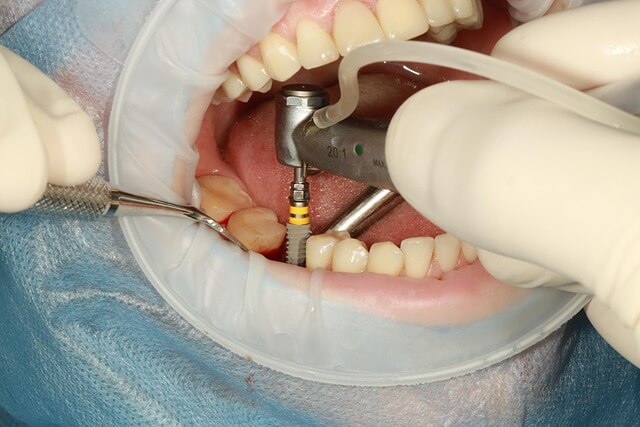

불소도포 원리와 치아 보호의 과학

불소도포란 불소 성분을 치아 표면에 바르는 방법으로, 치아의 겉면인 법랑질을 단단하게 만들어 줍니다. 이 과정은 충치를 일으키는 산이 법랑질을 약화시키는 것을 막아주는 역할을 하죠. 제가 실제로 불소도포를 받았을 때 느낀 건, 치아가 미끄럽고 매끄럽게 변한다는 것이었어요. 바로 그 표면 강화 효과 덕분입니다. 이런 변화는 며칠이 지나면 자연스럽지만, 내부적으로는 치아가 산에 훨씬 강해집니다.

불소도포 후 관리법, 효과 지속의 핵심

불소도포 후 관리가 절반입니다. 도포 직후 30분간은 음식을 먹지 말아야 하고, 4시간 동안 양치를 피하는 것이 좋아요. 이렇게 해야 불소도포가 충분히 흡착됩니다. 저는 아이가 과자를 먹고 싶어 할 때마다 “이건 치아가 약을 먹는 시간이라서 지금은 안 돼”라고 설명해줬어요. 덕분에 아이도 자연스럽게 기다릴 줄 알게 됐죠.

불소가 완전히 자리 잡은 후에는 평소보다 더 부드러운 칫솔을 사용해 양치해 주세요. 너무 강한 압력으로 문지르면 도포 효과가 줄어듭니다. 또한 불소 치약을 함께 쓰면 시너지 효과를 볼 수 있습니다